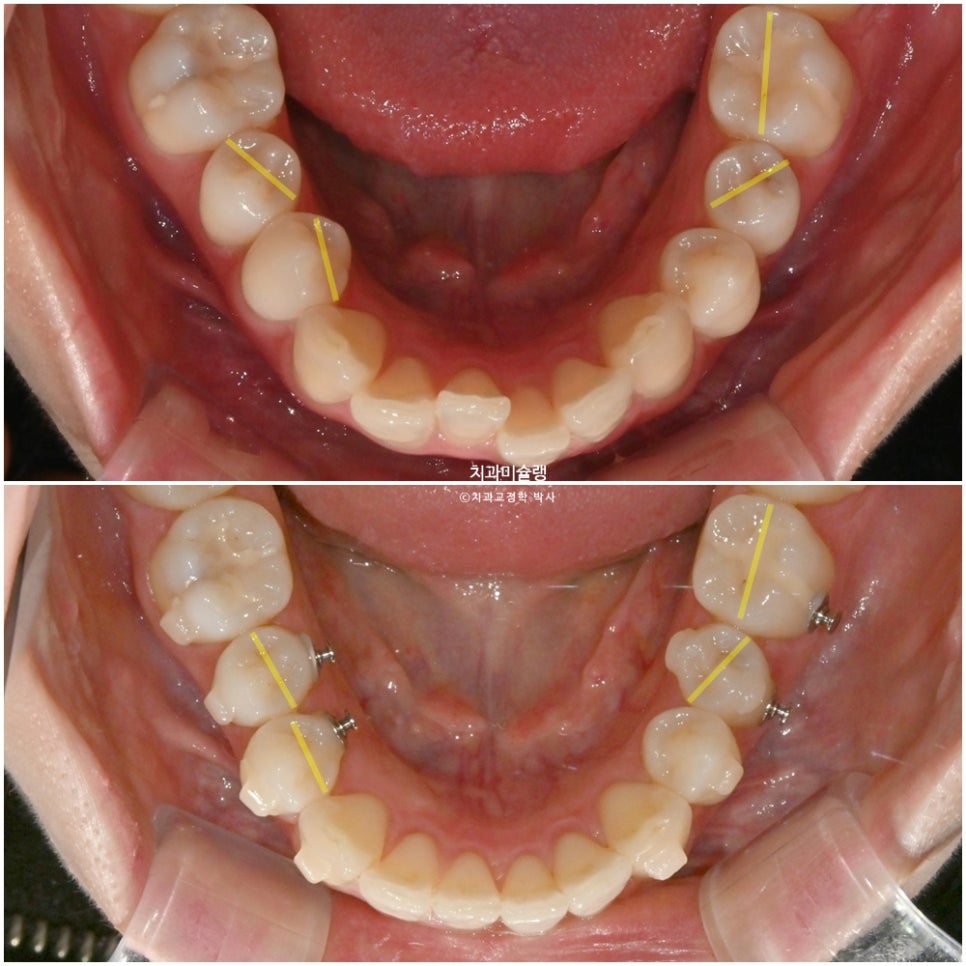

이 부가장치에 고무체인을 걸어놓음으로써 소구치의 회전이 첫세트에서 완료되었는데

4개월간의 회전 개선량을 표시해보면 이러합니다.

작은어금니 회전까지 완벽 개선되었습니다.